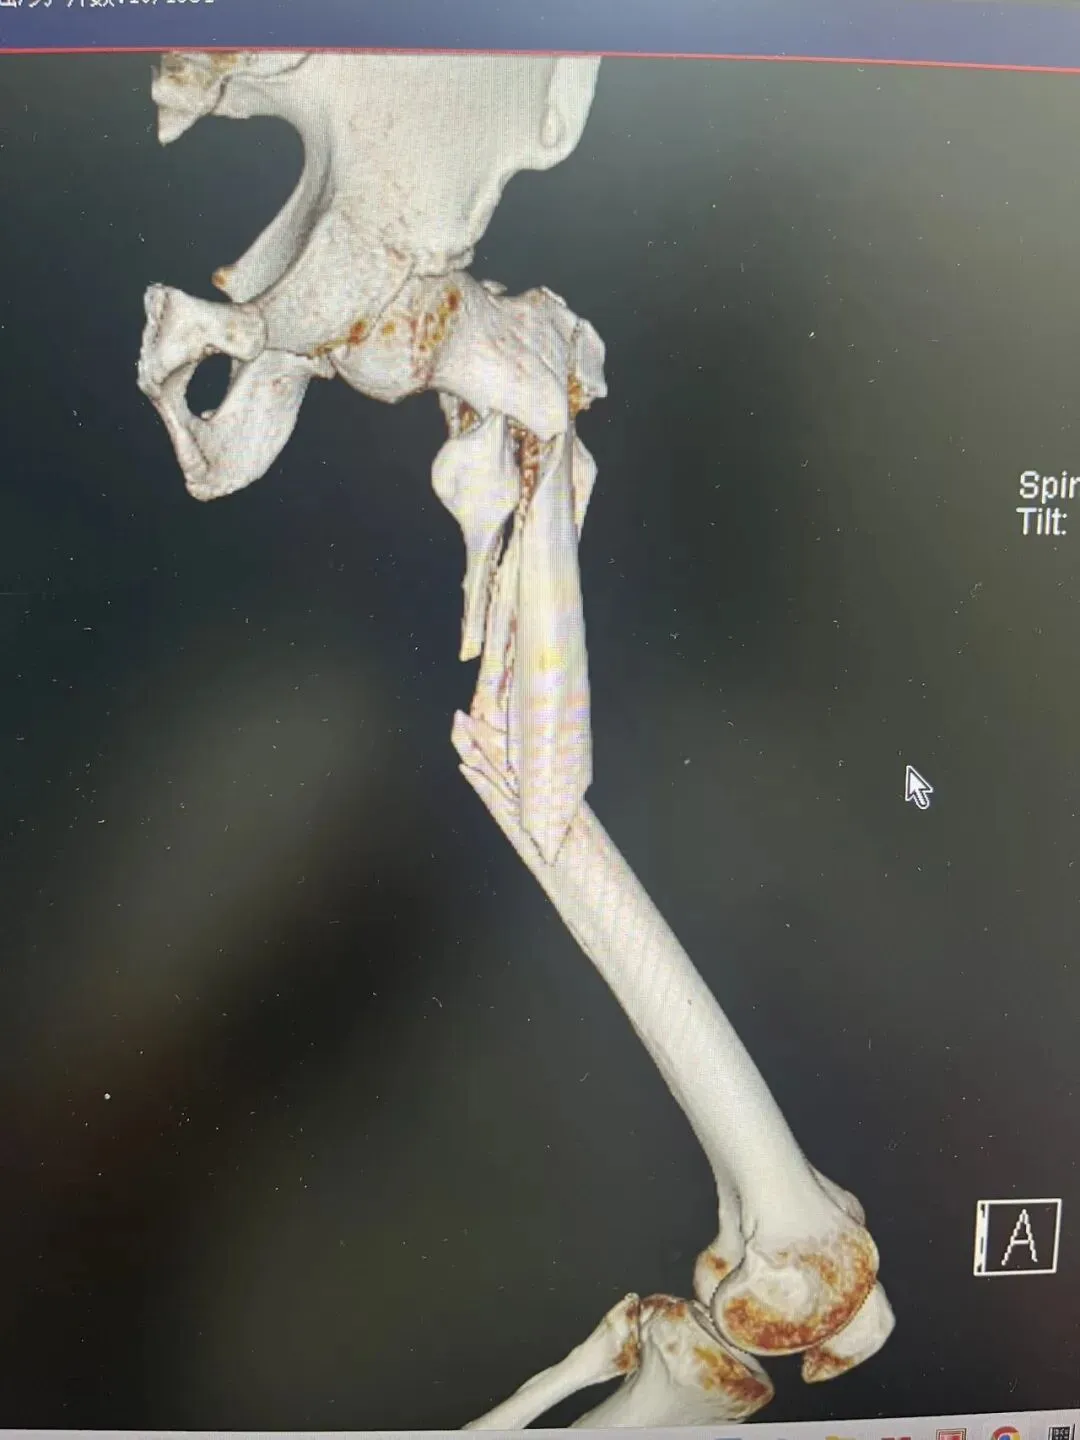

先看片子

中老年男性,高处坠落伤,如此长节段股骨近端骨折比较少见。手术治疗是必须的,患者等待期间血栓风险极高。而且患者卧床骨牵引期间护理极其不方便,给家人造成很大困惑为早点解决患者病痛,入院后积极抗凝预防血栓,伤后第3天手术治疗。我们选择PFNA闭合复位内固定。手术还算顺利。

术后侧位看骨折块间仍有较大距离,但是我们不担心,骨折力线、颈干角没有太大问题。